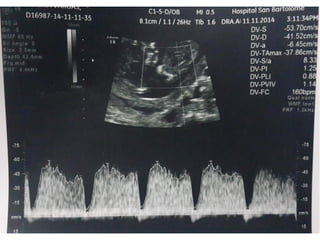

DUCTUS VENOSO

• Vaso pequeño que conecta la vena umbilical con la

proximidad de la aurícula derecha. Tiene un papel crítico

dirigiendo la sangre oxigenada al cerebro fetal

• Un 20% de la sangre oxigenada de la placenta sobrepasa el

hígado y se dirige al corazón fetal. Entra en la aurícula

derecha y luego a la izquierda, a través del foramen oval.

• De la aurícula izquierda pasa al ventrículo izquierdo y luego

a la aorta

DUCTUS VENOSO • Vasopequeño que conecta la vena umbilical con la proximidad de la aurícula derecha. Tiene un papel crítico dirigiendo la sangre oxigenada al cerebro fetal • Un 20% de la sangre oxigenada de la placenta sobrepasa el hígado y se dirige al corazón fetal. Entra en la aurícula derecha y luego a la izquierda, a través del foramen oval. • De la aurícula izquierda pasa al ventrículo izquierdo y luego a la aorta

VALORACIÓN DV • Semanas11+0-13+6 y la LCC entre 45-84 mm. El feto no debe moverse. • El tamaño de la imagen debe ser tal que el tórax y abdomen fetal ocupen toda la pantalla. Se debe obtener un corte sagital medio del tronco fetal. • Se debe usar el Doppler color para demostrar la vena umbilical, el ductus venoso y el corazón fetal. La ventana del Doppler pulsado debe ser pequeña (0,5-1,0 mm) y debe situarse en la zona de aliasing normalmente en amarillo

VALORACIÓN DV • Elángulo de insonación debe ser menor de 30 grados. • El filtro debe ser de baja frecuencia (50-70 Hz), para permitir la visualización de la onda completa. • La velocidad de barrido debe ser alta (2-3 cm/s), para obtener una forma más ancha y poder evaluar mejor la onda A.